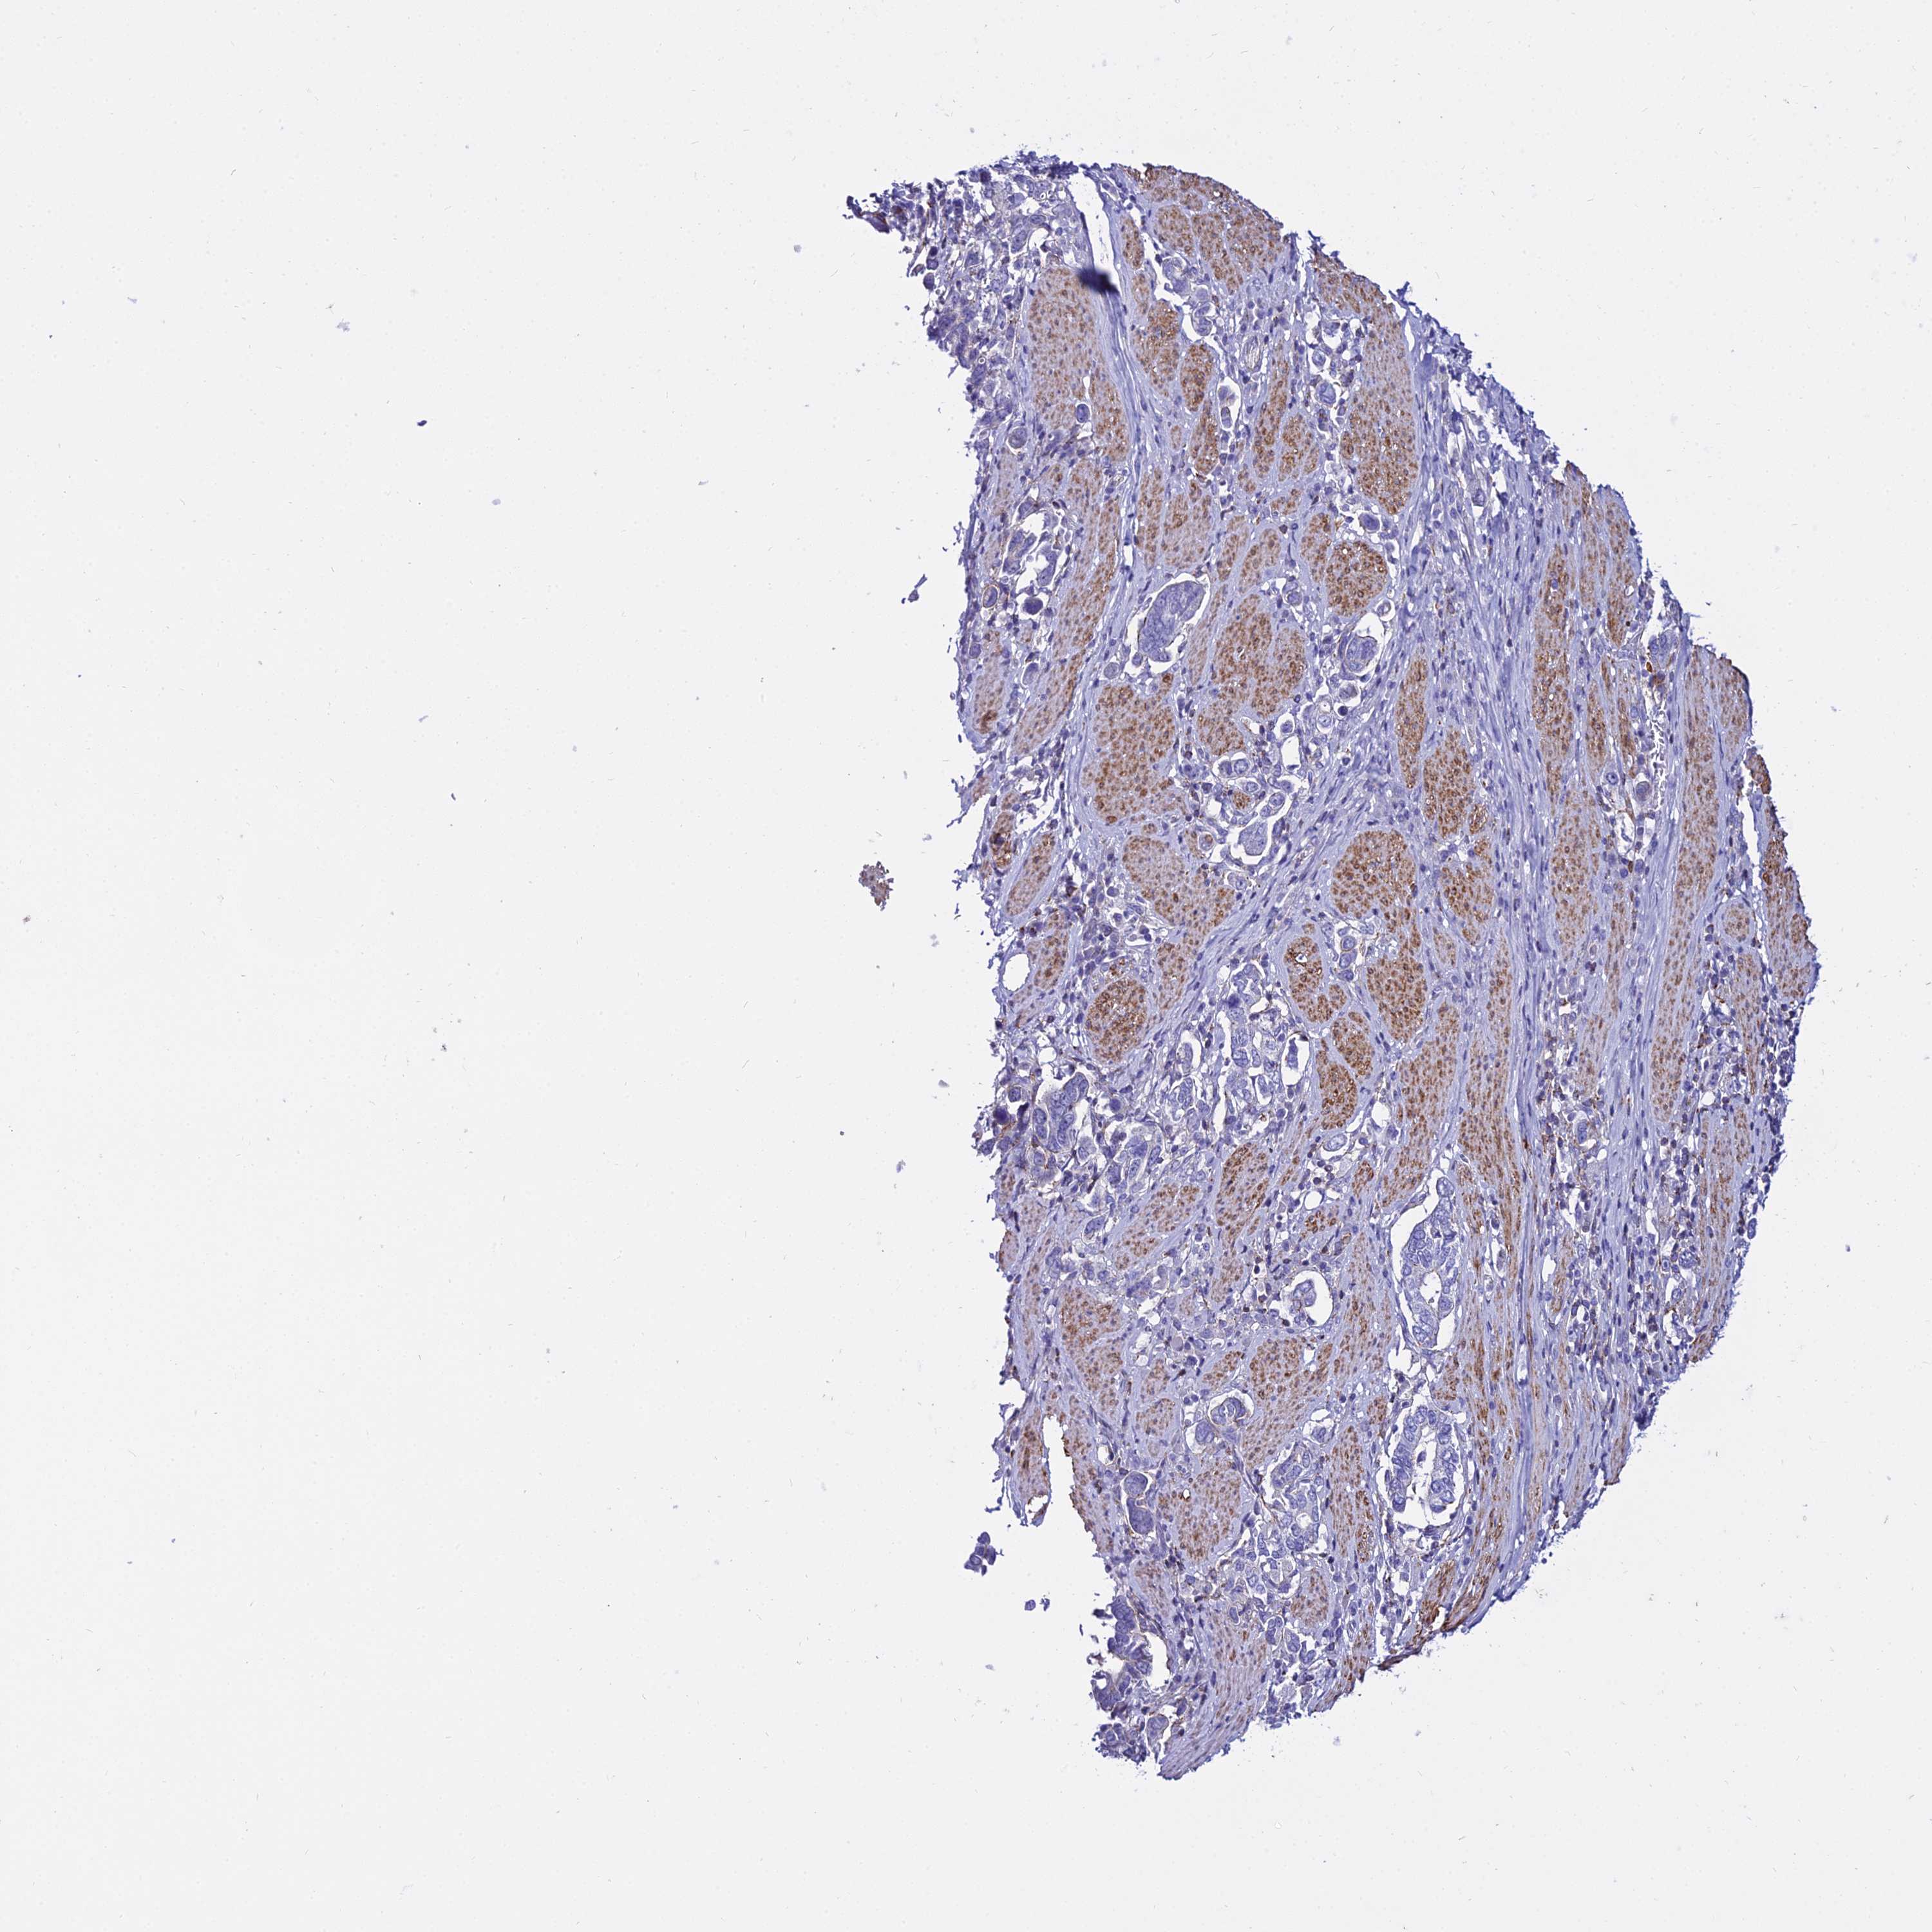

STOMACH CANCER - Protein expressioni

A mouse-over function shows sample information and annotation data. Click on an image to view it in a full screen mode. Samples can be filtered based on level of antibody staining by selecting one or several of the following categories: high, medium, low and not detected. The assay and annotation is described here.

Note that samples used for immunohistochemistry by the Human Protein Atlas do not correspond to samples in the TCGA dataset.

Antibody stainingi

Antibody staining in the annotated cell types in the current human tissue is reported as not detected, low, medium, or high, based on conventional immunohistochemistry profiling in selected tissues. This score is based on the combination of the staining intensity and fraction of stained cells.

Each image is clickable and will lead to virtual microscopy that enables deeper exploration of all samples and also displays staining intensity scores, fraction scores and subcellular localization as well as patient and tissue information for each sample.

Antibody HPA045884

Staining

High

Medium

Low

Not detected

Intensity

Strong

Moderate

Weak

Negative

Quantity

>75%

75%-25%

<25%

None

Location

Nuclear

Cytoplasmic/membranous

Cytoplasmic/membranous,nuclear

Adenocarcinoma, NOS